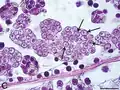

Plasmodium falciparum, the causative agent of malaria, infecting blood cells

Plasmodium falciparum, the causative agent of malaria, infecting blood cells -

The remaining alveolates are grouped under the clade Myzozoa, whose common ancestor acquired chloroplasts through a secondary endosymbiosis from a red alga.[69] One branch of Myzozoa contains the apicomplexans and their closest relatives, a small clade of flagellates known as Chrompodellida where phototrophic and heterotrophic flagellates, called chromerids and colpodellids respectively, are evolutionarily intermingled.[69] In contrast, the apicomplexans (Apicomplexa) are a large (>6,000 species) and highly specialized group of obligate parasites who have all secondarily lost their photosynthetic ability (e.g., Plasmodium). Their adult stages absorb nutrients from the host through the cell membrane, and they reproduce between hosts via sporozoites, which exhibit an organelle complex (the apicoplast) evolved from non-photosynthetic chloroplasts.[70][42]: 600

- In apicomplexans, a haploid sporozoite is released into the host, penetrates a host cell, begins the infection and transforms into a meront that grows and asexually divides into numerous merozoites (a schizogony called merogony); each merozoite continues the infection by multiplying. Eventually, the merozoites differentiate (gamogony) into female (macrogametocytes) and male (microgametocytes) that generate gametes, which in turn fuse (sporogony) into a diploid zygote that grows into a sporocyst. The sporocyst then undergoes meiosis to form sporozoites that transmit the infection.[70][162]